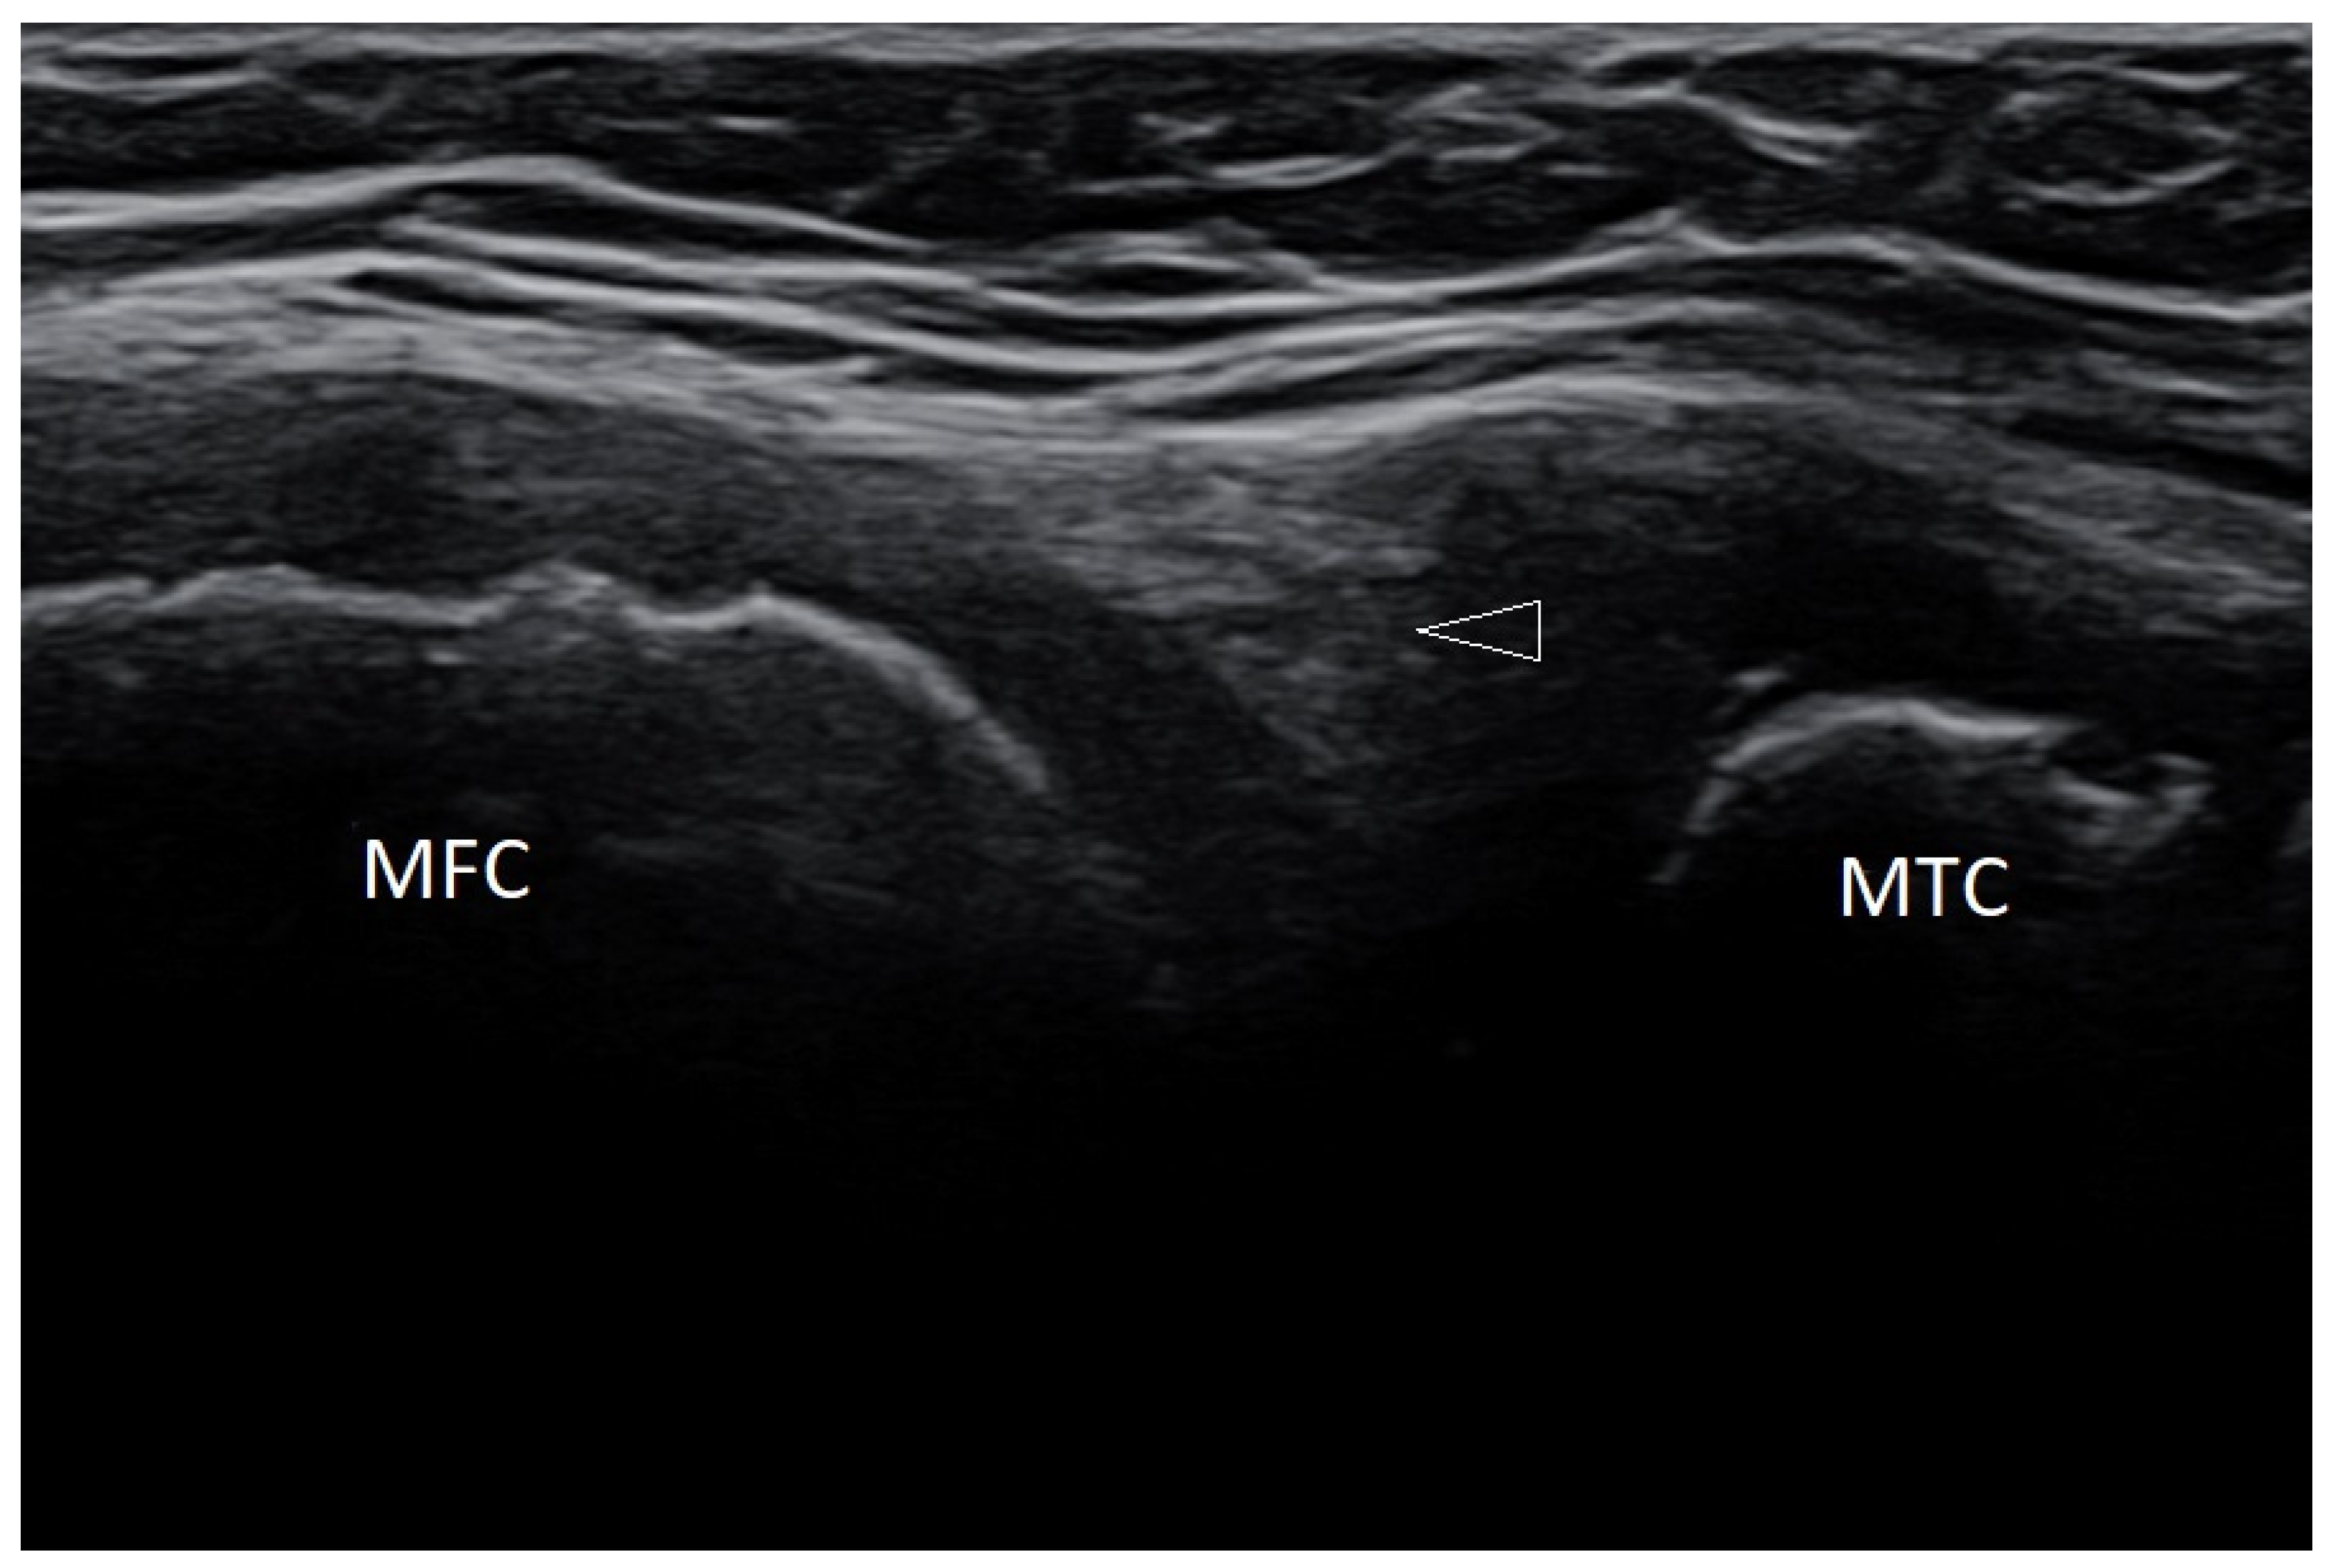

3.2.1. Osteochondritis Dissecans

3.2.7. Baker’s Cysts